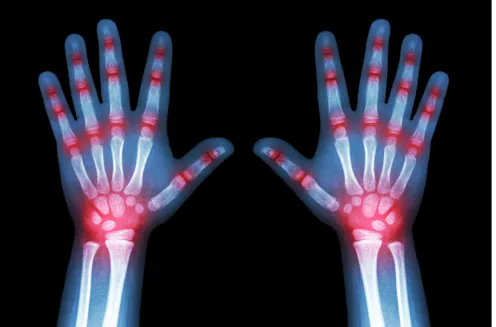

Arthritis is usually associated with older people but kids can suffer too. Juvenile idiopathic arthritis (JIA) is the most common type of arthritis in children. It affects about about 1 in 1,000 kids under 16 in the UK (roughly 15,000 children), and causes joint pain and inflammation in the hands, knees, ankles, elbows and wrists – although it can affect other body parts, too.

There’s no cure for JIA. Pain can be managed through treatments to ease symptoms, reduce pain and swelling, and prevent joint damage. Medications such as immunosuppressant methotrexate and biological medicine etanercept are widely used. But these treatments can have side effects, such as decreasing ability to fight infection.